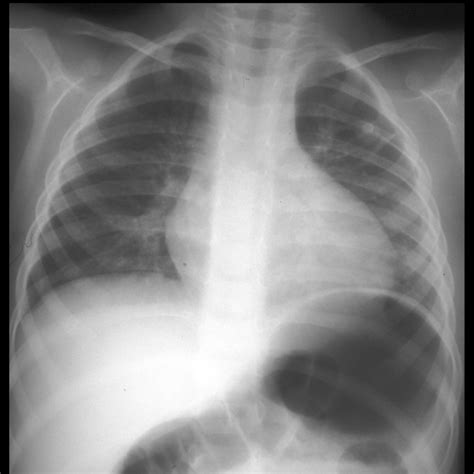

Most individuals with a Right Subclavian Artery Aberrant live their entire lives without ever knowing they have this condition. It is often discovered incidentally during imaging for unrelated issues, such as a chest X-ray or a CT scan. However, for a small percentage of the population, the anatomy of the vessel—specifically its path behind the esophagus—can lead to distinct clinical manifestations.

When an aberrant vessel is suspected, clinicians rely on non-invasive imaging techniques to map the vascular architecture. These diagnostic tools are critical for determining the path of the artery and its relationship to surrounding structures.